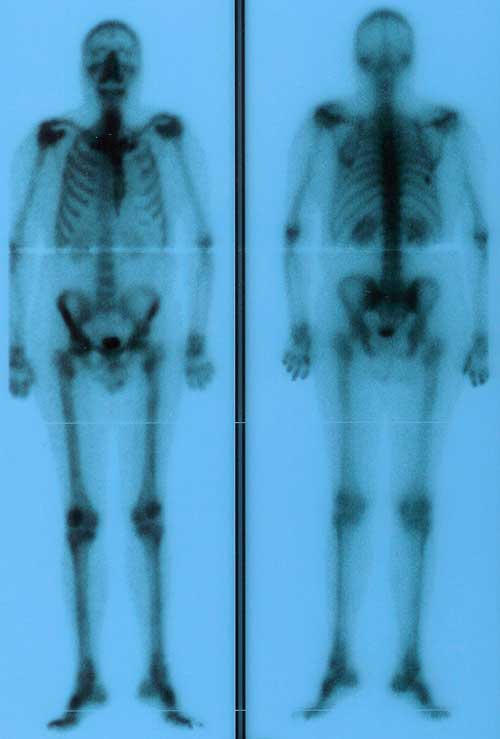

Día 10. Hoy tengo la Gammagrafía. Por la mañana tempranito al Hospital me ponen el contraste y me dicen que vuelva en tres horas. Así que me da tiempo de ir a casa, dormir una hora y volver. Me hacen la Gammagrafía y me dicen que no pueden darmela ya que no hay nadie para firmarla. Que o bien pase otro día a recogerla o que se la pasan directamente al oncólogo.

Mi mujer se acerca al Hospital por los resultados de la Gammagrafía:

Procedencia: SERVICIO DEL PROPIO CENTRO (CONSULTA ONCOLOGIA MEDICA H.G. PRUEBAS MEDICINA NUCLEAR)

Trazador: Tc99mHMDP Dosis: 666 MBq

INFORME:

Se realiza estudio gammagráfico de cuerpo completo, donde se sigue visualizando un incremento focal de captación de moderada intensidad en 8º arco costal posterior derecho, que si descarta existencia de antecedente traumático que lo justifique podría ser sugestiva de proceso infliltrativo.

CONCLUSION

Estudio de similares características al realizado anteriormente (8/04/2010) |

Pincha en la imagen para ampliar

Gammagrafía 10-11-2010 |